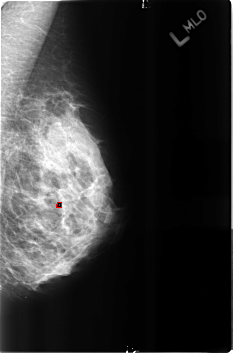

B_3162_1.LEFT_MLO

FILE: B_3162_1.LEFT_MLO.OVERLAY

TOTAL_ABNORMALITIES 1

ABNORMALITY 1

LESION_TYPE CALCIFICATION TYPE LUCENT_CENTER DISTRIBUTION N/A

ASSESSMENT 2

SUBTLETY 4

PATHOLOGY BENIGN_WITHOUT_CALLBACK

TOTAL_OUTLINES 1

BOUNDARY